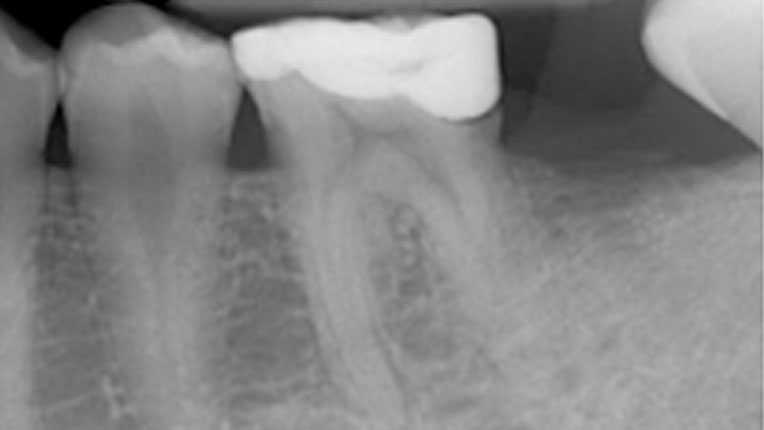

La Endodoncia es el procedimiento que se realiza para conservar el diente , que de otra manera tendría que ser extraido.

Disponemos del mejor Equipo en cuanto a personal y tecnología, ultimas tecnicas en Tratamientos sin dolor. Equipo de Endodoncia de Ultima Generación , sistema rotatorio con localizador integrado y Endodoncistas extensamente formados.

La mayoria de las Endodoncias se realizan en una sesion , es decir en una cita , existen determinados casos , por ejemplo cuando la infección es muy grande que es recomendable hacerlo en dos sesiones.

¿Por que en dos sesiones?, porque sino que no se puede obturar el mismo día con un material definitivo ya que puede causar mayores problemas, por eso es preferible en determinados casos hacerlo en dos sesiones.